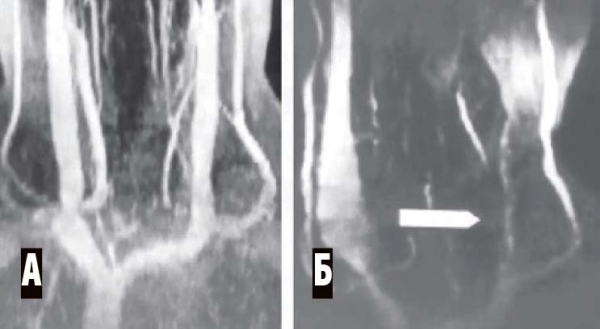

Магнитно-резонансная венография (аппараты МРТ имеют специальную программу для такого исследования). Исследуются синусы головного мозга, а также вены шеи. Всегда сравниваются правая и левая стороны (см. рис. 4, 5).

Рисунок 5. МР-венография при тромбозе синусов. А — левая сторона, обнаружено отсутствие сигнала от левых поперечного и сигмовидного синусов (признак тромбоза). Б — правая сторона, кровоток по синусам в норме.

Рисунок 6. МР-венограмма. Мышечная компрессия внутренней яремной вены. А — брахиоцефальные вены в норме, Б — сдавление левой внутренней яремной вены гипертрофированными нижними шейными мышцами (уровень сдавления показан стрелкой). Противоположная внутренняя яремная вена компенсаторно расширена.